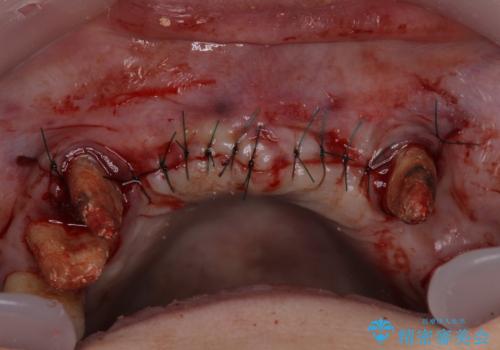

歯周外科処置を行ったことで歯周ポケットはなくなり、毎回のブラッシングの度に嫌な思いをしていた出血は認められなくなりました。

上下前歯の見え方を気にされており、歯だけをみると大変長くなりましたが、笑ったときの口元は自然な外見となり、患者様には大変満足していただきました。